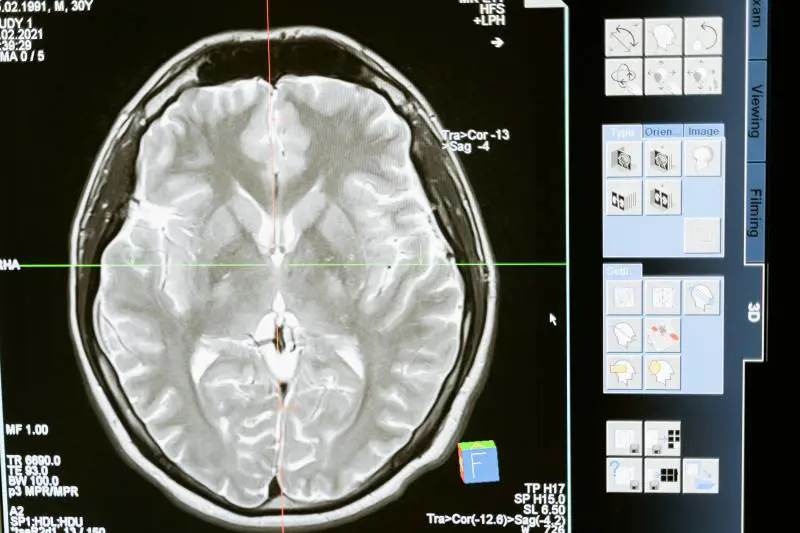

Lo studio condotto da UniBa ha infatti dimostrato che le reti genetiche che supportano il funzionamento delle cellule del nostro cervello disperdono il rischio di schizofrenia sull'intero genoma implicato. Gli autori hanno identificato nei neuroni eccitatori degli strati superficiali della corteccia le cellule implicate nel disturbo.

È stato così possibile identificare i geni che sono collocati nelle specifiche regioni del cervello che sono implicate nella malattia. E ciò permette di modulare un trattamento farmacologico più mirato. Grazie a questo studio si potrà prendere in considerazione geni e aree del cervello che non si pensavano prima d’ora di essere implicate.